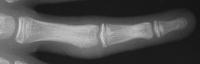

Late result:

Click for larger image